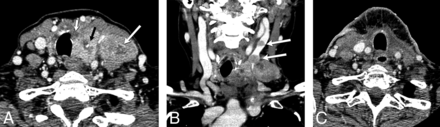

A 60-year-old man with history of neck pain for 1 month and neck CT demonstrating a large left neck mass biopsied as anaplastic thyroid cancer, stage IVC. A, CECT demonstrates a heterogeneously enhancing solid tumor involving the left thyroid lobe and isthmus, with extension to the tracheoesophageal groove and esophageal invasion (arrow). B, Tumor encases the internal carotid artery (large white arrow), and there is direct extension to the prevertebral space, supraglottis (small white arrow), oropharynx, and floor of mouth (black arrow). C, FDG-PET shows intense radiotracer uptake within the left neck tumor with extension to the mediastinum, and there, nodal metastasis to the right neck. D, Pretreatment sonography with Doppler demonstrates a hypoechoic, solid, diffusely infiltrative mass involving the left lobe with increased vascular flow.

A, Lymphoma: CECT demonstrates a homogeneously enhancing mass diffusely enlarging the right thyroid lobe (small arrows) without calcification or necrosis. There is displacement of midline structures without organ invasion. Enlarged right level IV node (large arrow) enhances homogeneously without calcification, necrosis, or cystic change. B, Papillary thyroid carcinoma: CECT demonstrates a heterogeneously enhancing right thyroid lobe mass (black arrow) with foci of calcification and without necrosis, displacing the midline structures toward the left without organ invasion. Metastatic right level IV node (white arrow) demonstrates calcification and cystic change. C, Anaplastic thyroid carcinoma: CECT demonstrates a necrotic right thyroid lobe mass (small white arrow) directly invading the esophagus (large white arrow) and internal jugular vein (black arrow), and there is encasement of the common carotid artery.